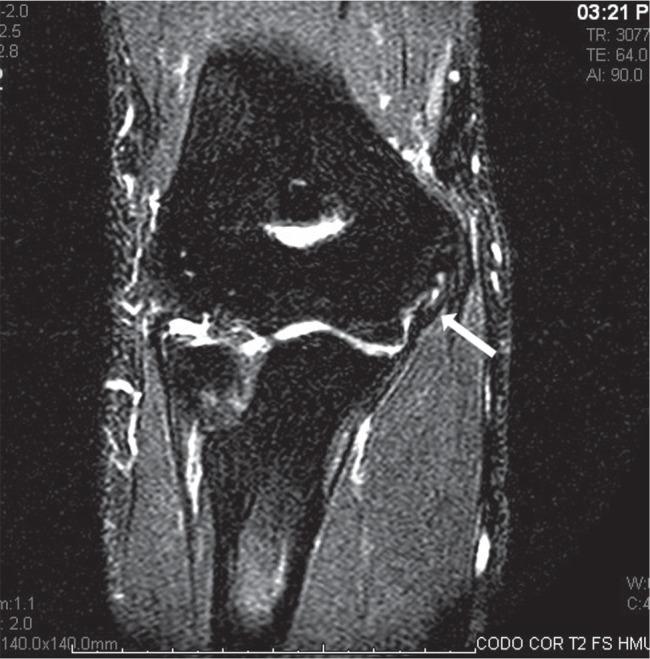

Medial elbow pain.

Medial elbow pain is uncommon when compared with lateral elbow pain.Medial epicondylitis is an uncommon diagnosis and can be confused with other sources of pain.Overhead throwers and workers lifting heavy objects are at increased risk of medial elbow pain.Differential diagnosis includes ulnar nerve disorders, cervical radiculopathy, injured ulnar collateral ligament, altered distal triceps anatomy or joint disorders.Children with medial elbow pain have to be assessed for 'Little League elbow' and fractures of the medial epicondyle following a traumatic event.This paper is primarily focused on the differential diagnosis of medial elbow pain with basic recommendations on treatment strategies. Cite this article: EFORT Open Rev 2017;2:362-371. DOI: 10.1302/2058-5241.2.160006.